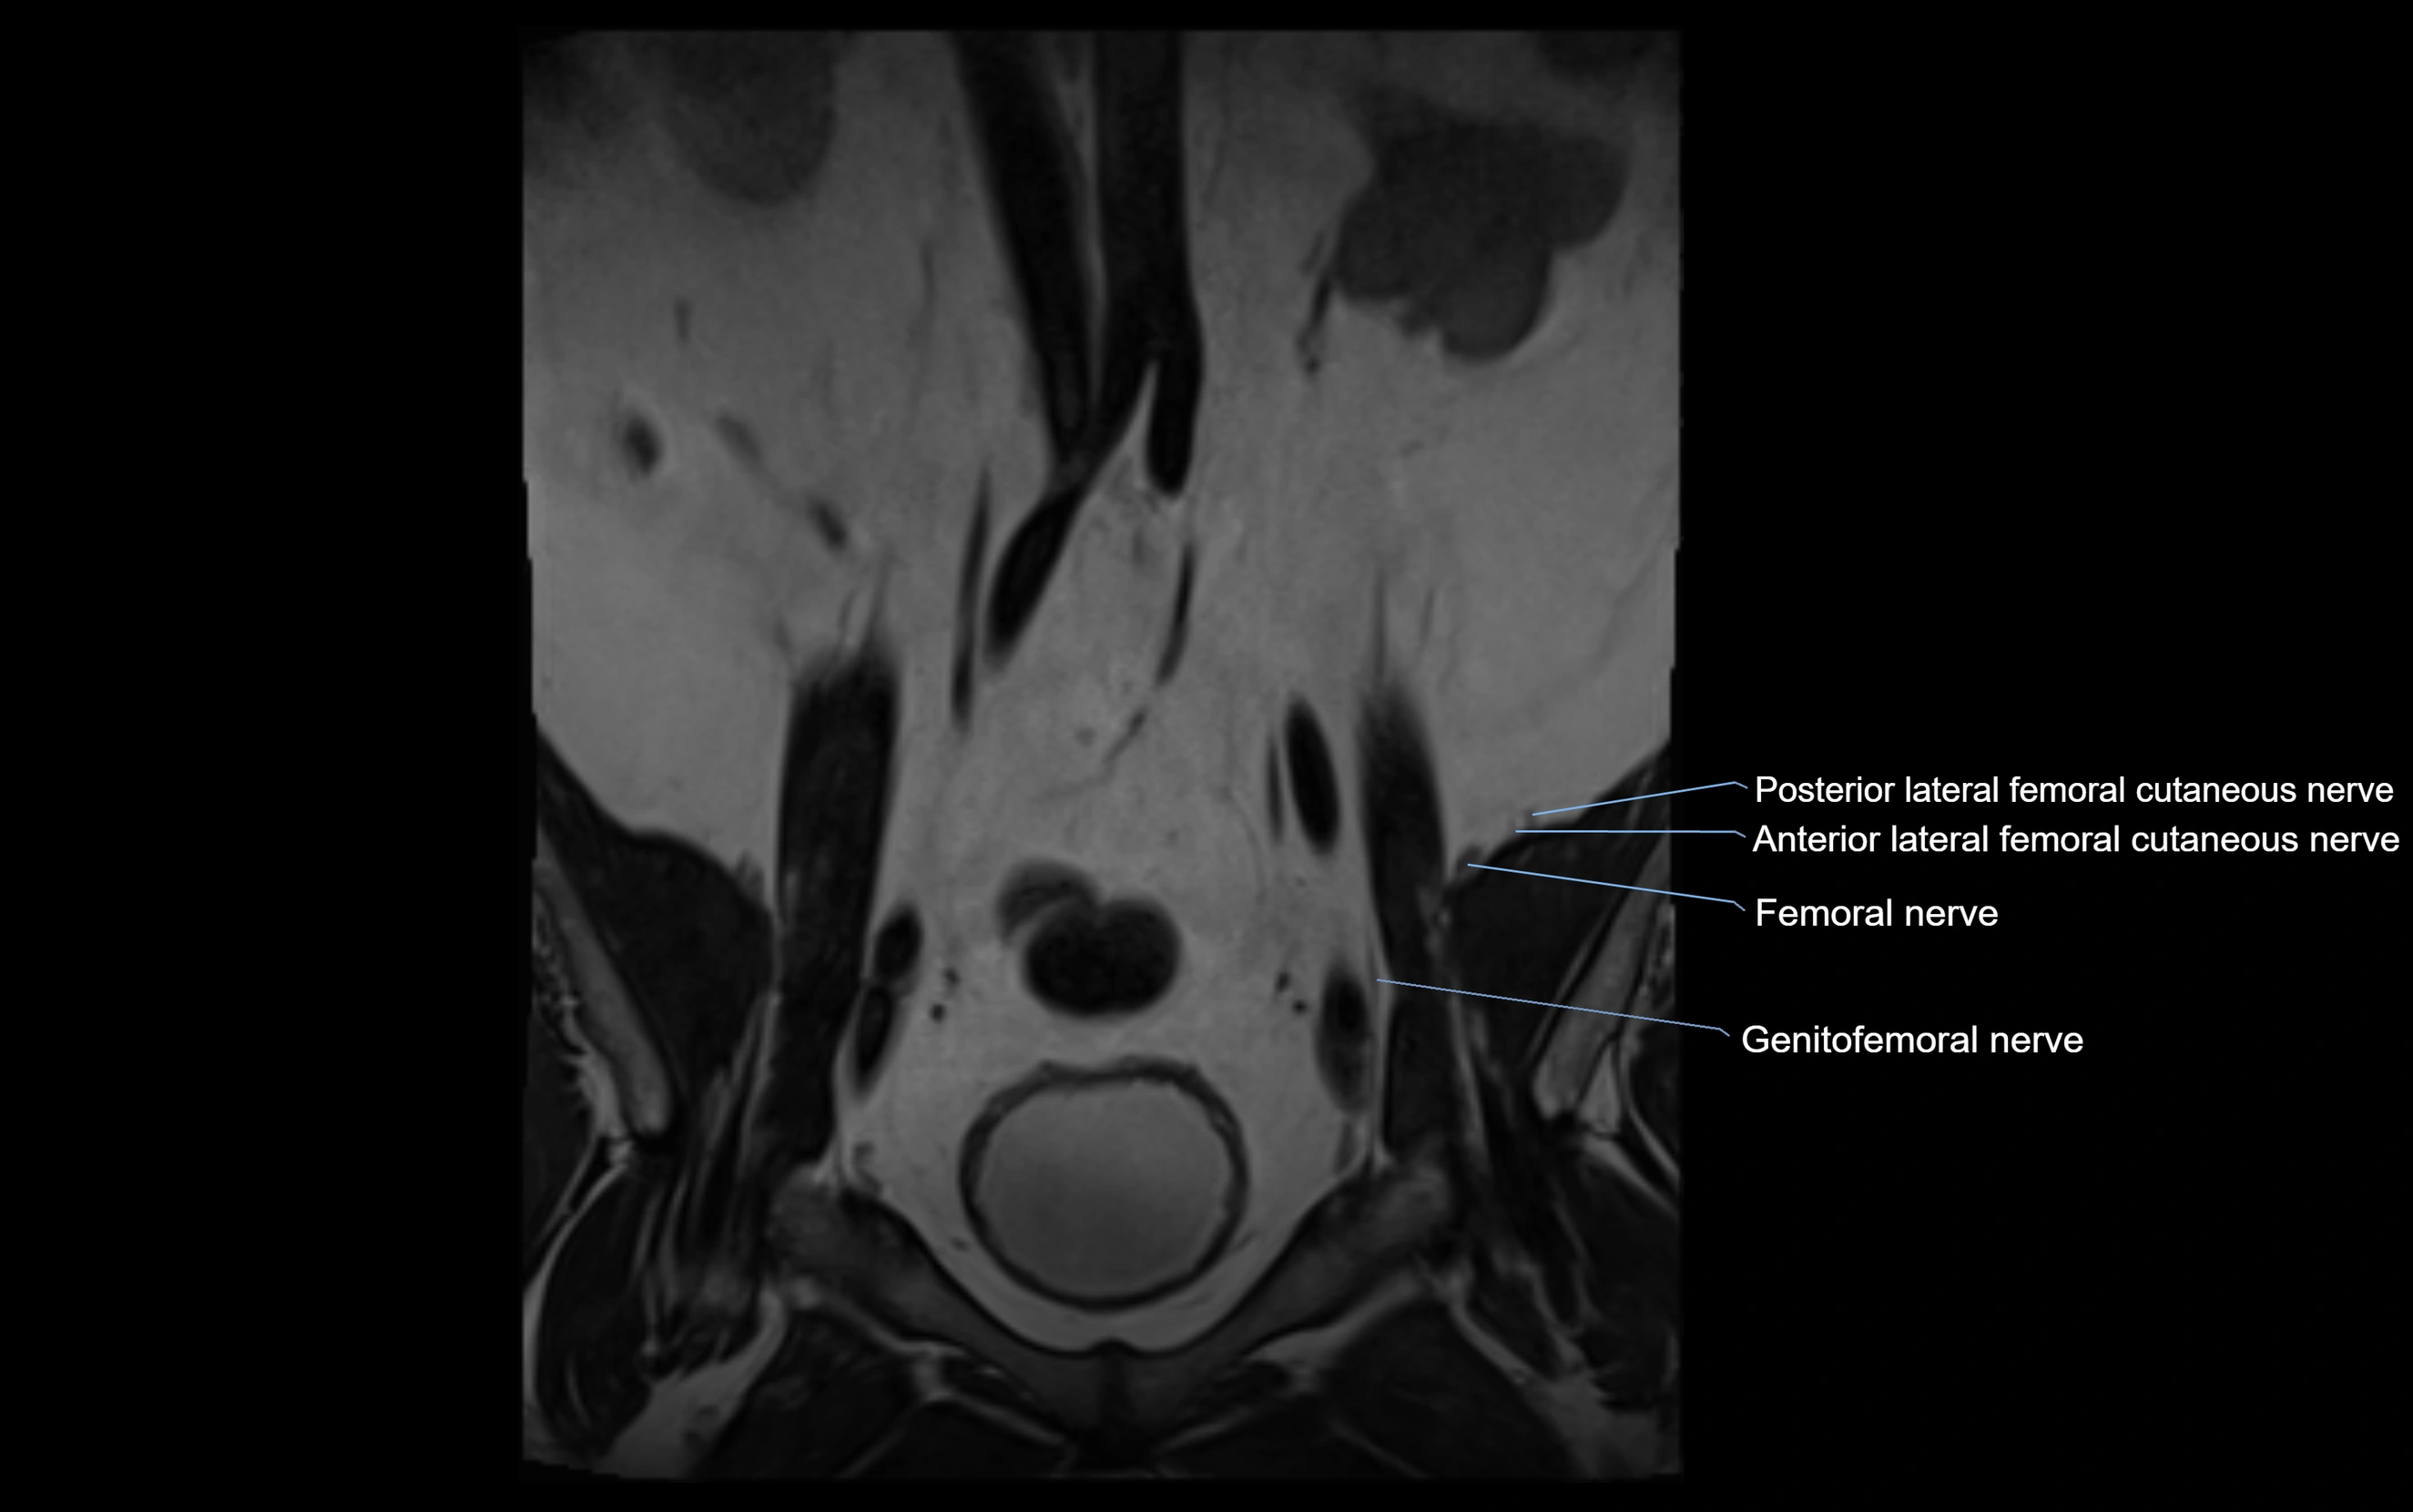

MRI image

image